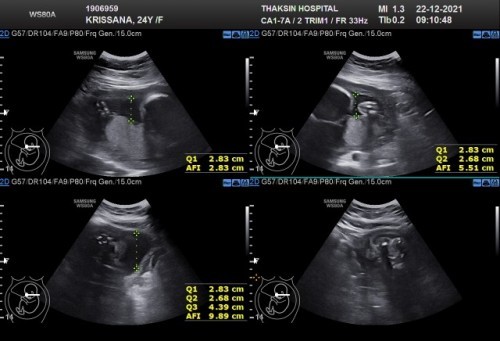

หมอบอกน้ำคล้ำค่อนข้างน้อย บ้านนี้กังวลมากเลยคะ ท้อง27วีคคะ อันตรายมากไหมคะ

น้ำคล่ำค่อนข้างน้อยดังวลมากคะ